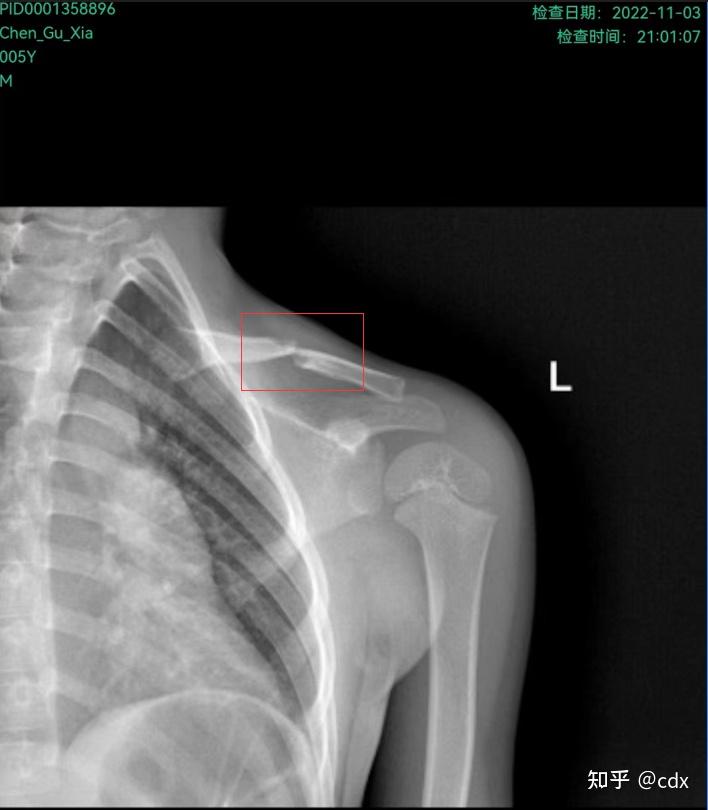

儿童锁骨骨折.五岁小朋友,右锁骨骨折,差点又被拉去手术,我们 - 抖音